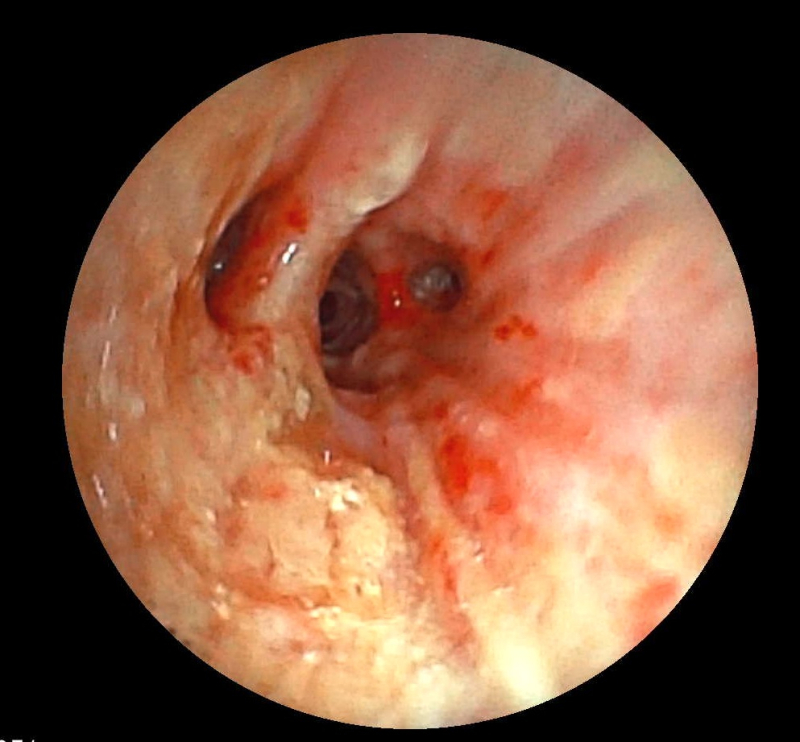

Ekip của bác sĩ CKI Phạm Thị Út Trang – Phó Trưởng Khoa Nội hô hấp đã phối hợp với bác sĩ gây mê hồi sức đã nhanh chóng tiến hành nội soi phế quản ống mềm, phát hiện dị vật góc cạnh khoảng 1cm là hạt kha tử hình bầu dục, bề mặt trơn nhẵn, hai đầu nhọn nằm chắn, gây bít tắc trong lòng phế quản gốc phải, ngay sát vị trí chia nhánh phế quản phân thùy- khu vực giải phẫu hẹp, góc rẽ nhánh phức tạp khiến việc gắp dị vật gặp khó khăn.  Ekip nội soi can thiệp đã khéo léo tiếp cận và thành công gắp dị vật ra khỏi lòng phế quản. Sau can thiệp, sức khỏe của bệnh nhân ổn định, thở dễ dàng, không còn cảm giác tức ngực, được xuất viện sau 24h theo dõi.

Ekip can thiệp nội soi phế quản thành công lấy dị vật ra khỏi lòng phế quản